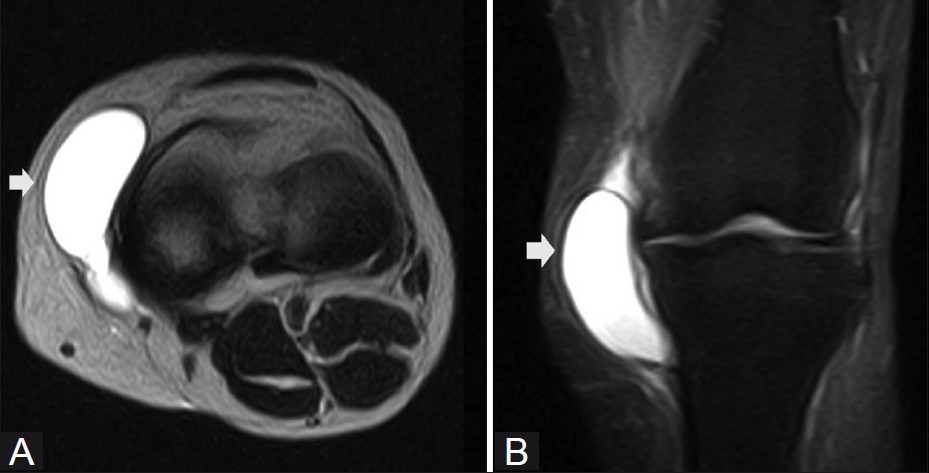

대부분의 정상적인 점액낭은 소량의 점액을 함유하여 MRI에서 잘 관찰되지 않지만, 염증성 변화에 의해 점액양이 증가되면 T1 영상에서 저신호 강도를, T2 영상에서 고신호 강도를 보이는 경계가 명확한 점액낭이 관찰된다.

△ 심층 슬개하 점액낭염(Deep infrapatellar bursitis)의 MRI 소견

△ 슬개상 점액낭염(Suprapatellar bursitis)의 MRI 소견